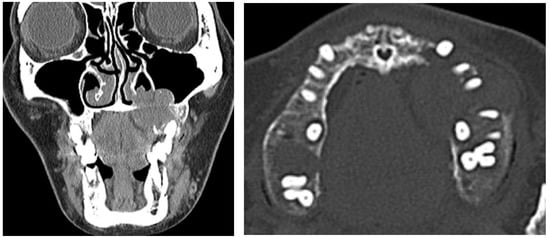

2.1. Clinical Presentation

2.2. Differential Diagnosis

2.3. Diagnosis and Management